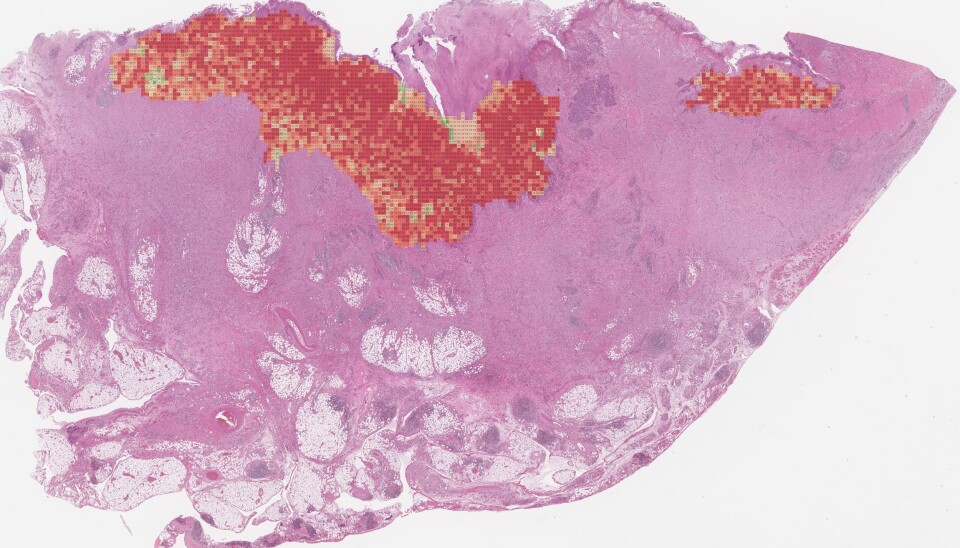

Through so-called deep learning, artificial intelligence has figured out how to distinguish tumours with a good prognosis from those with poor prognosis.

In the learning process, the machine has looked at millions of pictures from colon cancer tumours.

After self-training, artificial intelligence was given the opportunity to try new patients. And then even more patients, until it is now validated. For each patient, it analyzes approximately 6,000 images. The patients are recruited from many different countries, and the samples are prepared at various hospitals and digitized with different scanners.